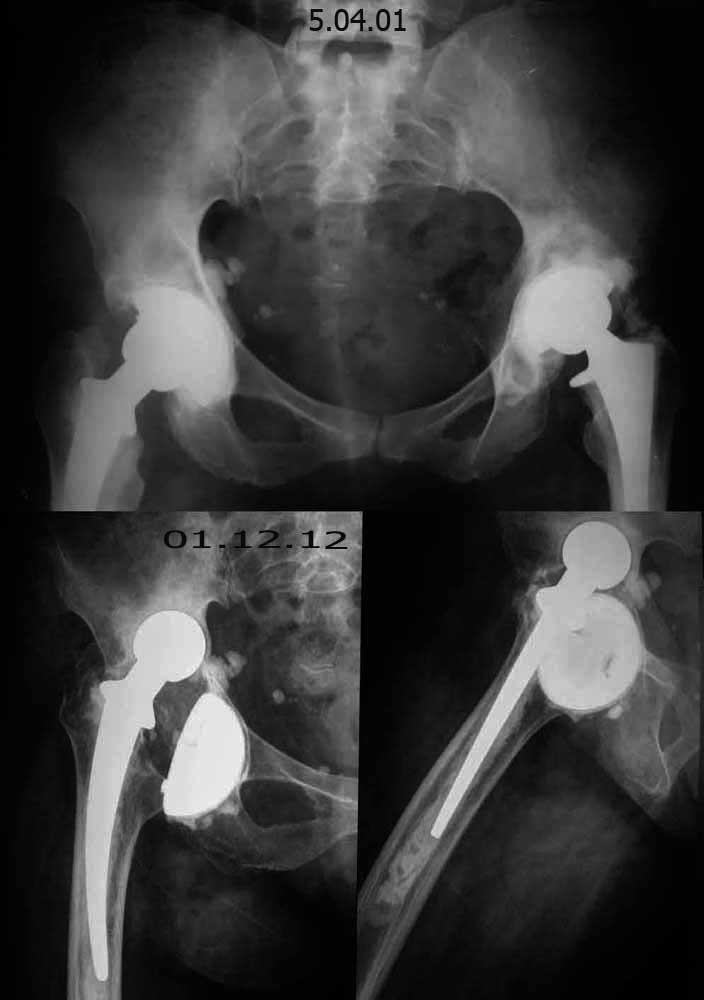

Уважаемые коллеги, помогите определиться с тактикой лечения! Больная Л. 56 лет, 20 лет страдает ревматоидным полиартритом. В 1987 году выполнена операция- артропластика левого тазобедренного сустава по Кулишу. В 1997 году оперирована - тотальное эндопротезирование правого тазобедренного сустава. В 1998 году оперирована - тотальное эндопротезирование левого тазобедренного сустава. 1,5 года назад больная упала, после чего стала отмечать боль в области правого тазобедренного сустава. Локально: правая нижняя конечность укорочена на 1-1,5см. по сравнению с левой. Движения в правом тазобедренном суставе: сгибание - 35-40º, разгибание-10º, отведение- 15º, приведение-10º, наружная ротация-20-25º, внутренняя ротация-0º. Движения в левом тазобедренном суставе: сгибание - 75-80º, разгибание-15º, отведение- 30º, приведение-20º, наружная ротация-25-30º, внутренняя ротация-20º.

Очень интересное наблюдение! Сформировалося нечто, похожое на гемипротезирование. Скажите пожалуйста, данное состояние в правом тазобедренном суставе причиняет ей боль или нет? Конечно оперировать такую больную будет очень тяжело, кровопотеря будет большая, приемлема ли ожидаемая кровопотеря с возмещением донорской кровью при её заболевании? Ну если решился бы я на операцию, несмотря на все риски, я бы в вертлужной части эндопротеза применил бы структурный трабекуллярный металл, которым заполнил бы имеющиеся дефекты вертлужной впадины (предварительно поняв, какие и каком объеме имеются дефекты) по КТ. Ну бедренный компонент, ревизионную ножку Вагнера (видеть бы состояние бедренной кости дистальнее ножки на протяжении) или может быть ножку цементной фиксации? надо подумать:)))

Речь идет о нестабильности вертлужного компонента спустя 15 лет после эндопротезирования. На мой взгляд, необходимо первым этапом исключить инфекцию, самое простое-пункция сустава с посевом полученной жидкости, желательно это сделать минимум двукратно, показатели периферической крови могут быть не совсем информативны учитывая основное заболевание. Далее все зависит от результатов исследования. Если они отрицательные, то надо планировать ревизию чашки, но с обязательным интраоперационным исследонием уже не только жидкости, но и тканей. Если и в этом случае Вы получаете отрицательные р-ты, то окончательно принимаете решение об обычной замене чашки. Я бы не мудрил, обычная чашка пресс-фитт фиксации но с обязательной дополнительной фиксацией винтами. Мне не совсем понятно какая установлена ножка - моноблок или модульная. Если моноблок, то возможны серьезные проблемы со стабильностью сустава и в этом случае надо быть готовым морально и технически к замене ножки. Если модульная, то надо не полениться найти головки с соответствующим конусом, учитывая старую модель ножки это как раз то время, пока будете ждать результаты посевов:-)